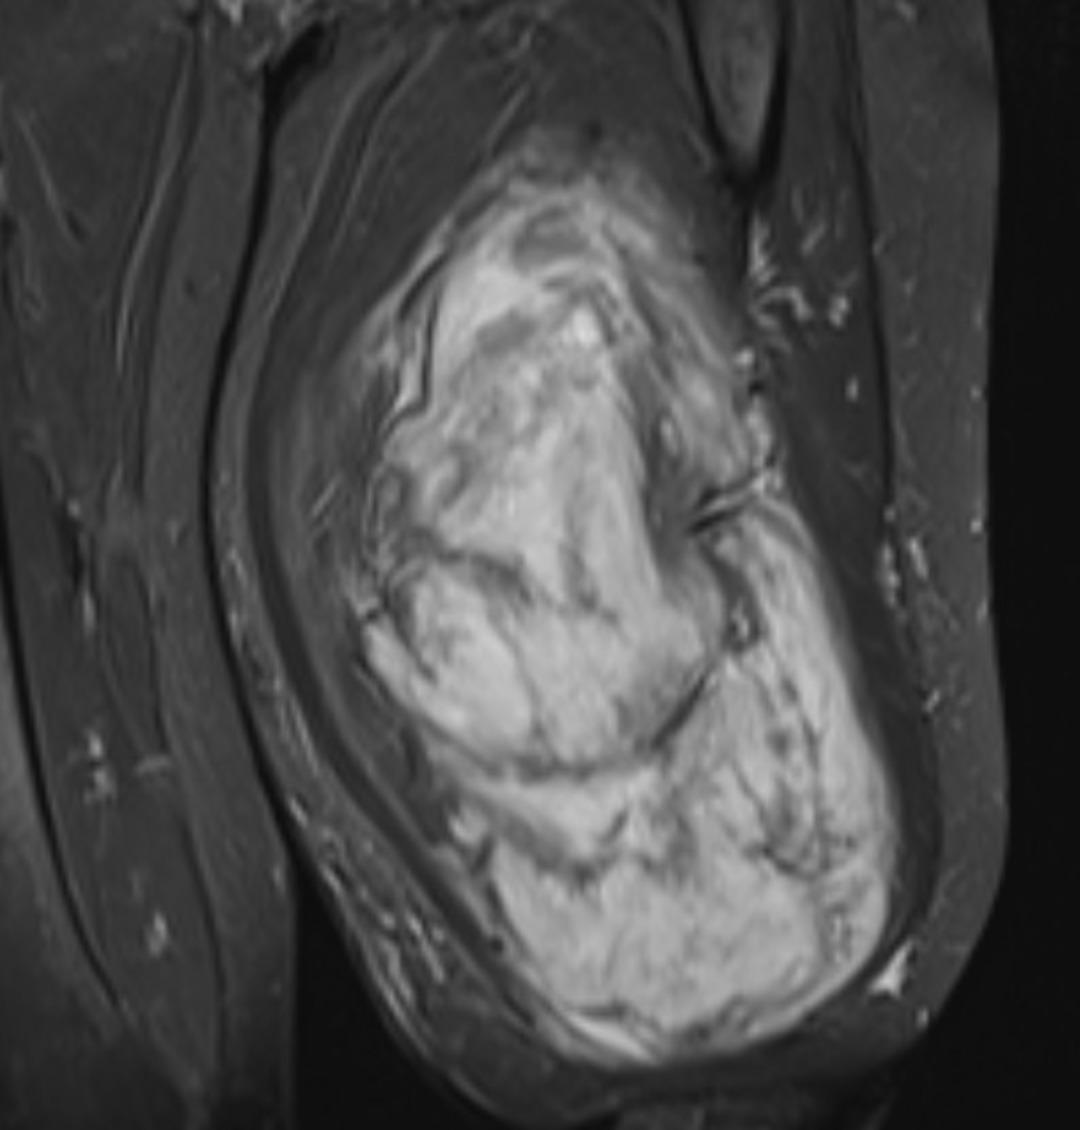

Muayenede yumuşak doku kitlesi olduğu değerlendirilen şişliğin alınması için Ortopedi ve Travmatoloji Anabilim Dalı Öğretim Üyesi Prof. Dr. Emin Özkul ve ekibi tarafından ameliyat kararı verildi. Yaklaşık 2 saat süren operasyonla kitlenin çıkarıldığı, kitlenin 5 kilo 668 gram geldiği belirtildi.

Prof. Dr. Emin Özkul, vücutta görülen kitlelere büyümeden müdahale edilmesi gerektiğini ifade ederek, “Hastamız 42 yaşında bir kadın. Komşu şehir Mardin’den geldi. Bölge hastanesi olduğumuz için bu tür hastalar Mardin’den, Şırnak’tan ve diğer illerden çok geliyor. Bu hastalara önerimiz; ‘küçük bir kitle, ağrısız bir kitlem var, ele gelen bir şişliğim var ama bunda ağrı olmadığı için herhangi bir şey olmaz’ dememeli. En yakın sağlık kuruluşuna başvurup en azından kitlenin bir öneminin olup olmadığını teyit edilmesi, bir uzman tarafından bunun doğrulanmasını istiyoruz. Bu hasta da 3 yıl önce fark edilmiş küçük bir kitle, zamanla çok büyük boyutlara, yaklaşık 6 kiloya varan boyutlara varmıştı. Neredeyse bütün bacak boyu yayılan bir kitlesi mevcuttu. Bu kadar büyümenin şöyle sıkıntıları oluyor, kişinin bacağında, kolunda fonksiyon kaybına, yeri geliyor ekstremite kaybına, yani bacağını kaybetmesine yol açabilecek sıkıntılara yol açıyor. Küçükken bunlarla baş etmek daha kolay. Kişinin ekstremitesinde, bacağında, kolunda bir sıkıntı yaratmadan bunları telafi etmek, bunları alıp çıkartmak, ameliyatla bunları tedavi etmek daha kolayken bu boyutlara vardığında kişinin bacağında, kolunda fonksiyon kaybı, sakatlık riski çok yüksek oluyor. Bu sebeple küçükken önleminin alınmasında yarar var” dedi.

Kitlelerin görülmesi halinde sağlık kuruluşlarına başvurulması gerektiğini belirten Prof. Dr. Özkul, “Hastamızda yaklaşık olarak 3 yıl önce şikayetleri başlamış. Sonra zaman içerisinde hızla büyüyen bir kitleye sahipti. Şanslıydı ki herhangi bir sinirine zarar vermemişti. Hayatına fonksiyon bozukluğu olmadan devam edebilecek. Bölgemize yaşayan ve ülkemizde yaşayan herkese şunu söylüyoruz. Küçük de olsa yumuşak doku kitlelerini önemsemeleri ve uzman görüşü almalarını öneriyorum. Bu hastadan 5 kilo 668 gramlık bir kitle çıkarttık. Bu benim mesleki yaşamım boyunca çıkarttığım en büyük kitlelerden bir tanesiydi. Biraz daha büyük boyutlara varmış olsa kişinin bacağını kurtarma şansınız olmuyor. Bu sebeple bunlara dikkat etmek gerekiyor. Hızlı büyüyen bir kitleniz var ise, ağrısız da olsa mutlaka ve mutlaka tedavi için en yakın sağlık kuruluşuna veya bizim üniversitemizin polikliniklerine başvurabilirsiniz” diye konuştu.